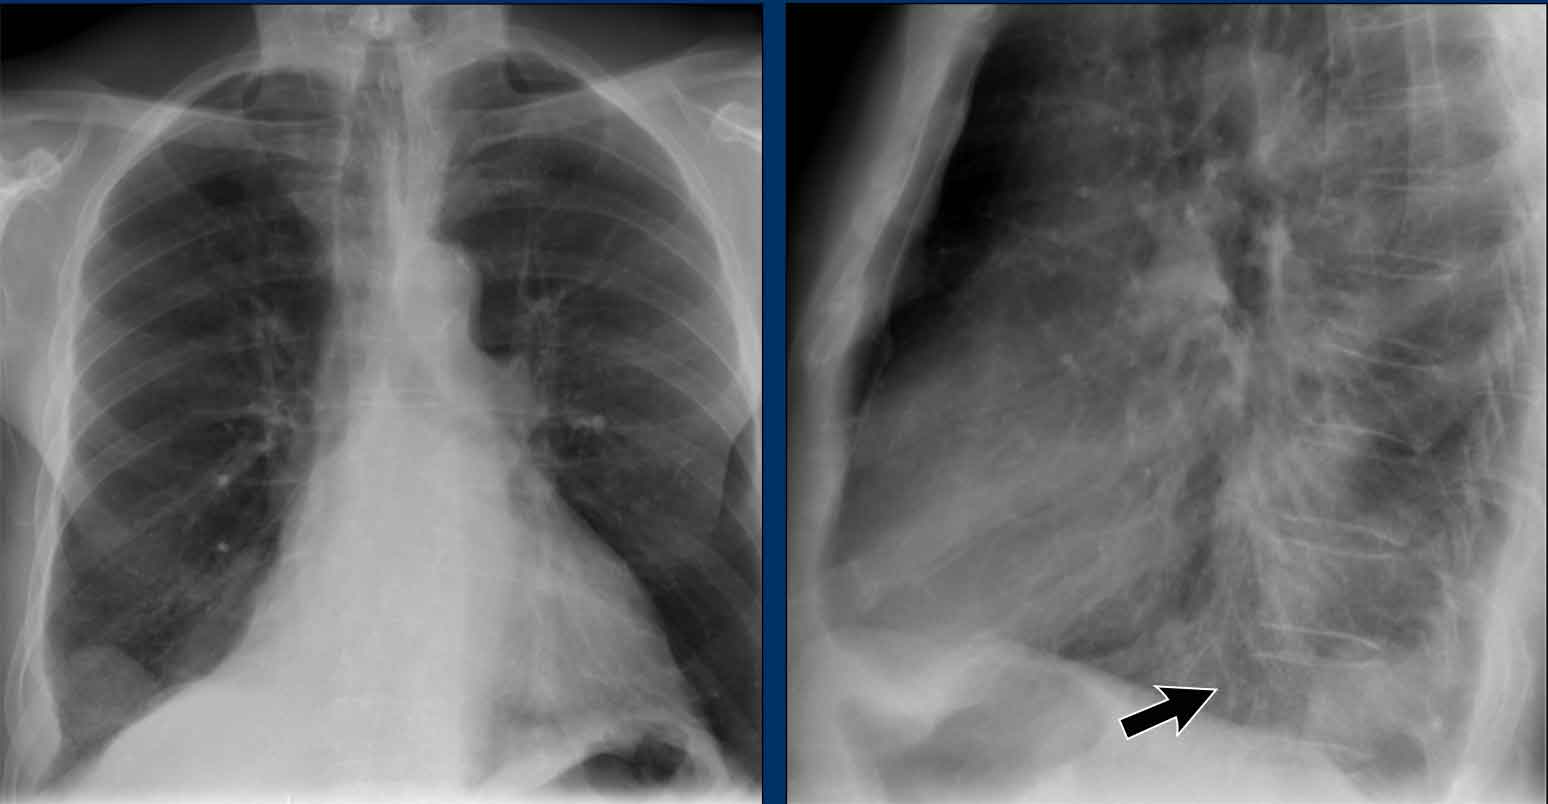

Case Example: Subtle Signs of Congestive Heart Failure

Begin by reviewing these current chest radiographs.

Based solely on these images, one might suspect congestive heart failure (CHF), though the findings are subtle.

Now review the previous study…

Scrolling between the current and prior films significantly increases diagnostic confidence in your diagnosis of congestive heart failure.

Key comparative findings include:

• Cardiac size: Slightly increased compared to the previous study; however, cardiomegaly was already present.

• Pulmonary vasculature: Mild vascular engorgement suggesting elevated pulmonary venous pressure.

• Interstitial markings: Subtle signs of interstitial edema .

• Pleural effusions: Bilateral small effusions, with subtle changes in the inferoposterior borders of the lower lobes, suggesting fluid accumulation.